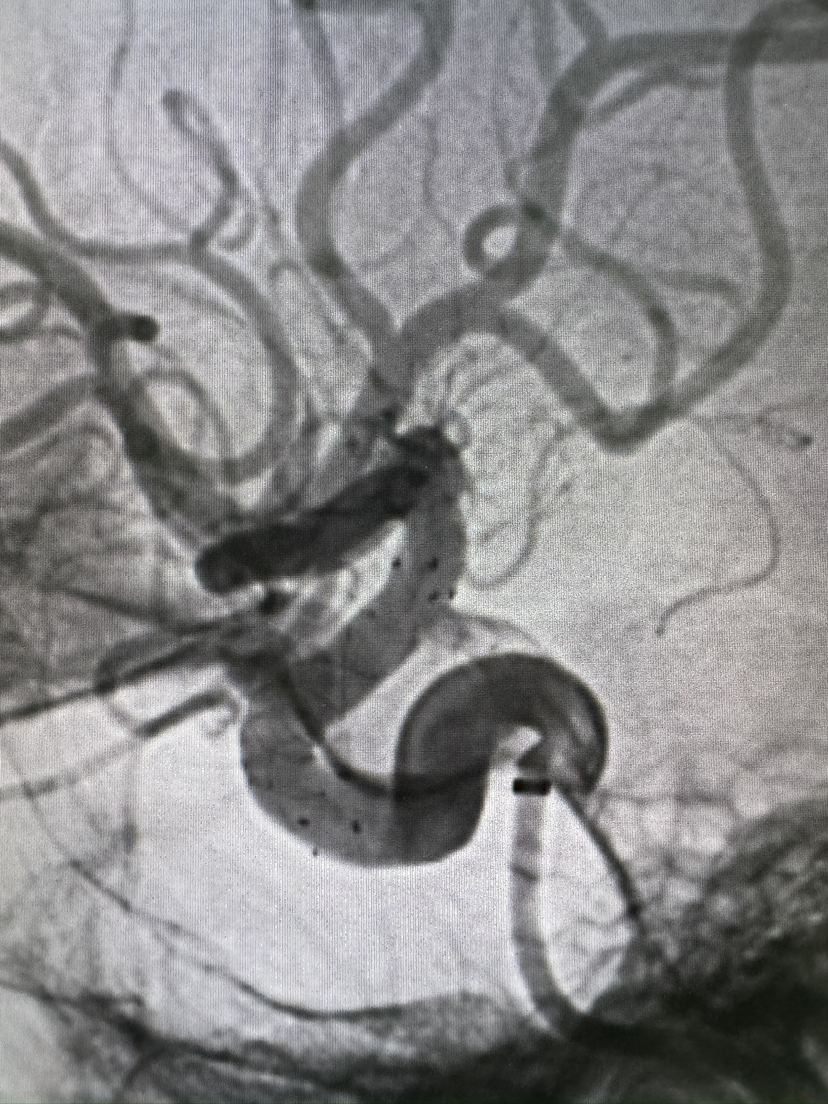

FRED血流导向密网支架栓塞眼动脉动脉瘤

#FRED®21 & FRED®27 血流导向密网支架

密网支架

动脉瘤

眼动脉